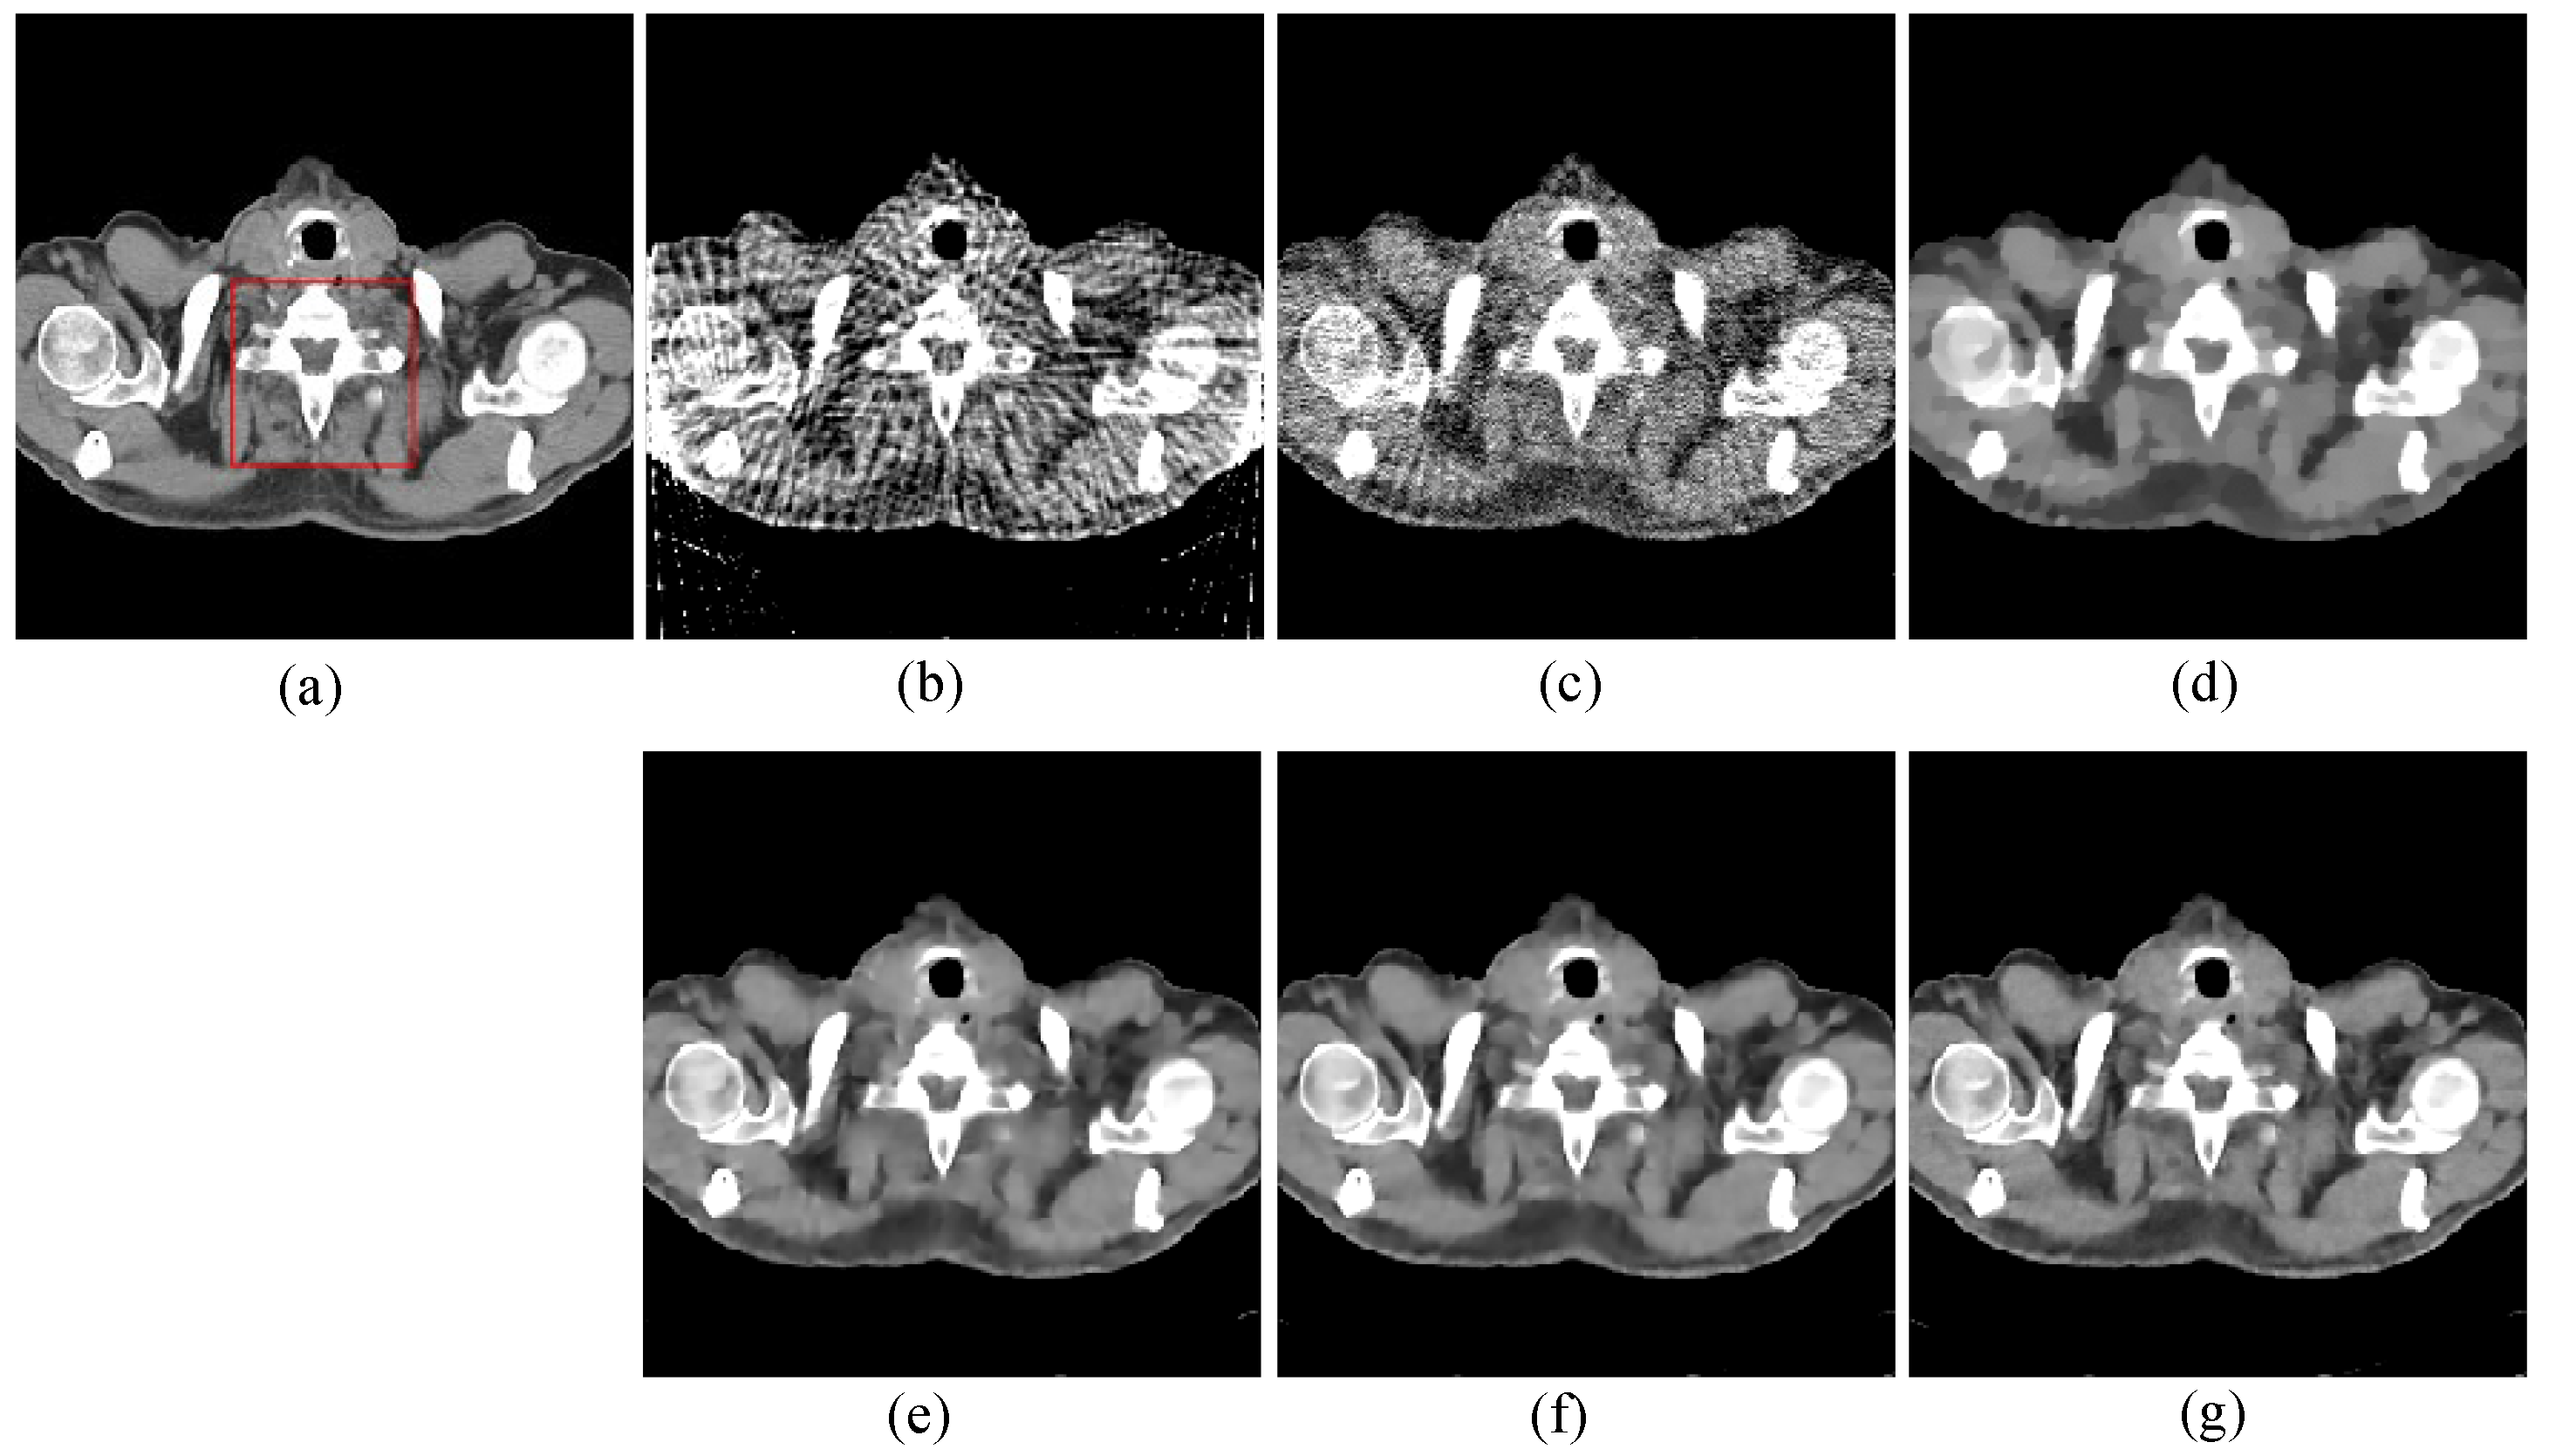

The first image reconstruction experiment is using a pelvic image to show the feasibility of our algorithm for SVCT reconstruction, as shown in Figure 1. We extracted 80, 64, and 48 views from a full scan and selected parameters empirically. The parameters are set as follows: a = 0.5, γ1 = 0.3, and γ2 = 0.08. Figure 2, Figure 3 and Figure 4 show the ground truth and reconstruction images via FBP, OS-SART, TV, PICCS, TVPI-G, and our method NPICCS. From these figures, it is evident that our algorithm outperforms the other methods in terms of recovering image structures and suppressing noise. Specifically, the FBP and OS-SART results (as shown in Figure 2b,c, Figure 3b,c and Figure 4b,c) contain high levels of noise and artifacts, while TV results (as shown in Figure 2d, Figure 3d and Figure 4d) are characterized by blurring and staircasing effects. The PICCS and TVPI-G methods provide better results than the other approaches because of the introduction of prior information, but image edges are missing as shown in Figure 2e,f, Figure 3e,f and Figure 4e,f. At the same time, it can be seen that our method is able to preserve image edges and suppress noise effectively, as shown in Figure 2g, Figure 3g and Figure 4g.

To compare the recovery of reconstructed image details and edge information, we selected two regions of interest (ROIs) from the 48-view and 64-view reconstructed images and zoomed in to show. The ROIs are labelled with red box as shown in Figure 2a and Figure 3a. The corresponding zoomed-in results are shown in Figure 5. As can be seen from the figure, our algorithm can reconstruct some small image structures shown by the arrows, which are difficult to see by other algorithms. Also, we find that our algorithm performs better in edge retention.

Figure 3. 64 views reconstruction results of pelvic image: (a) ground truth, (b) FBP, (c) OS-SART, (d) TV, (e) PICCS, (f) TVPI-G, and (g) NPICCS. The display window is [−150 250] HU.

Applsci 13 10320 g003

Figure 4. 80 views reconstruction results of pelvic image: (a) ground truth, (b) FBP, (c) OS-SART, (d) TV, (e) PICCS, (f) TVPI-G, and (g) NPICCS. The display window is [−150 250] HU.

Applsci 13 10320 g004

Figure 5. The ROIs from 48-views and 64-views reconstruction results. The first row is from 48-views ROI. The second row is from 64-views ROI. (a) ground truth, (b) FBP, (c) OS-SART, (d) TV, (e) PICCS, (f) TVPI-G, and (g) NPICCS. The display window is [−150 250] HU.

Applsci 13 10320 g005